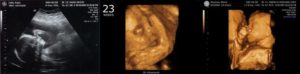

УЗИ на 23 неделе беременности

Акушеры-гинекологи рекомендуют пройти второе УЗИ не позднее 22 недели беременности, но если по каким-то причинам вы опоздали, то пройти ультразвуковое исследование можно сейчас.

На 23 неделе уже можно определить пол ребенка, а также убедиться в том, что его развитие соответствует сроку беременности.

Двойня на 23 неделе беременности

Каждый ваш малыш на этой неделе весит почти 500 гр и имеет длину 28-29см. Из-за периода интенсивного роста вашей двойни в ближайшие недели вы можете испытывать довольно сильный дискомфорт.

Малыши на этом сроке уже активно двигаются и вы должны ощущать их движения каждый день. Большинство беременных двойней на 23 неделе еще не могут точно определить, какой из малышей двигается в данный момент. Это нормально.